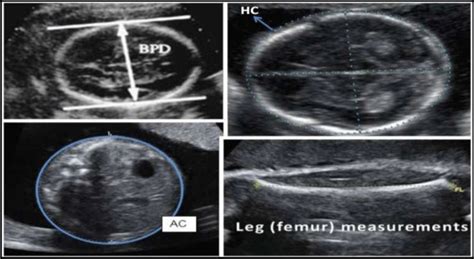

• BPD (Biparietal Diameter): This measures the distance across your baby’s head, from one side to the other. It’s basically the width of the head. Think of it like measuring the widest part of your baby’s skull. This measurement is crucial because it helps estimate the gestational age, especially in the early stages of pregnancy. Doctors use it to make sure the baby’s head is growing at a healthy rate. Variations in BPD can sometimes indicate potential issues, so it’s a key measurement to keep an eye on. BPD is not just a single measurement; it is an important marker of overall health and development. The accurate measurement helps in determining the stage of pregnancy.

• HC (Head Circumference): As the name suggests, this is the measurement around your baby’s head. Think of it like measuring your baby’s hat size, if they had one! Similar to BPD, HC is an important indicator of head growth and helps estimate the gestational age. Doctors use HC to make sure the baby’s head is growing appropriately. Head circumference is a crucial factor in the overall assessment of fetal well-being, providing valuable data to determine potential complications, and tracking the baby’s growth trajectory during pregnancy. Monitoring head circumference can help detect any abnormalities, such as too much or too little fluid, or problems with the brain.

• AC (Abdominal Circumference): This measures the circumference of your baby’s abdomen. Essentially, it’s a measurement of the baby’s belly. AC is particularly useful for assessing fetal weight and overall growth. It gives doctors an idea of how well your baby is nourished and developing. It can highlight potential problems like growth restriction or excessive growth. AC is used to monitor the nutritional status of the fetus . It’s a key indicator of your baby’s overall health and well-being. AC will also help in estimating fetal weight and assessing the baby’s overall growth.

• FL (Femur Length): This measures the length of your baby’s femur, which is the thigh bone. FL helps in estimating fetal age and assessing skeletal development. Think of it as measuring your baby’s leg length. This measurement can provide insight into the baby’s growth. FL provides important information, especially when it is coupled with other measurements. Monitoring FL helps assess the baby’s bone development and overall growth. The FL measurement is an excellent indicator to assess the baby’s health. It is also an important indicator in the detection of any development issues.